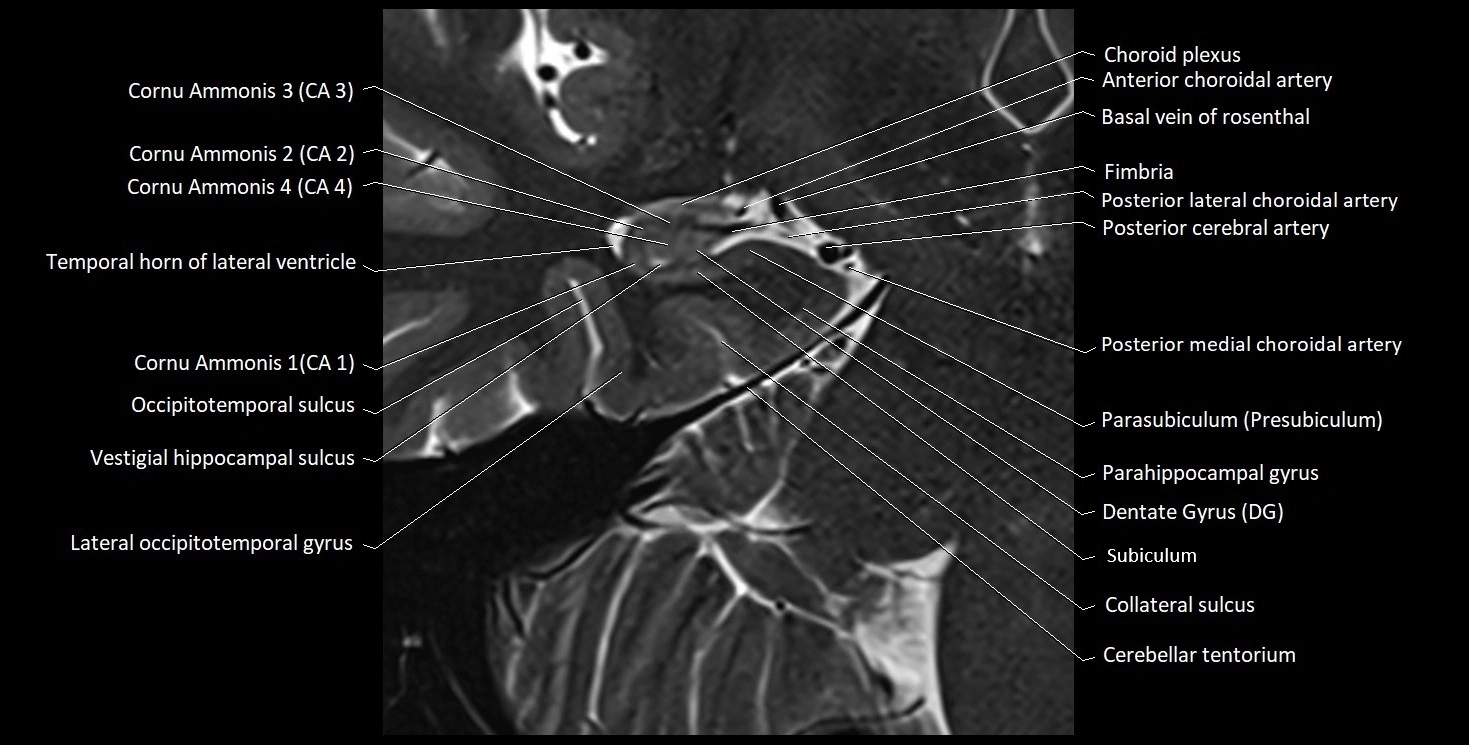

MRI images

image